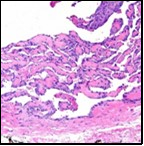

On microscopy, superficial squamous epithelial surface is intact. Sub-epithelial connective tissue stroma exhibits slit-like, vascular spaces. Upon extended magnification, multiple, intravascular papillary projections encompassed within a hyalinised stroma are discerned. Centroidal calcification appears in combination with intravascular, papillary endothelial cell proliferation, lined with singular layer of endothelial cells devoid of cytological atypia6, 7.

Characteristically, the vascular neoplasm denominates numerous papillae within blood vessels. Papillae are coated with singular or dual layer of flattened endothelial cells with an encompassing hyalinised, fibrous tissue core. Vascular lumen is distended with thrombosis. Foci of haemorrhage with fibrinous and purulent exudate are discerned. Tumour perimeter depicts inflammatory granulation tissue. Cholesterol clefts and focal reactive bone formation may concur. Extraneous squamous epithelium may be discontinuous and ulcerated. The neoplasm is devoid of features of malignancy4, 6.

Numerous micro-calcifications can be observed within the lesion which may engender vascular occlusion and tissue necrosis6. Figure 1, Figure 2, Figure 3, Figure 4, Figure 5, Figure 6, Figure 7, Figure 8.

Figure 1 Papillary endothelial hyperplasia elucidating papillary articulations layered with a single layer of endothelial cells and a commingling of fibrinous, thrombotic exudate 10.